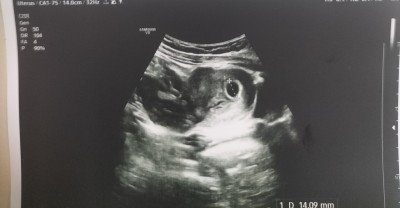

Dün gece karın ağrısı ile acile gittim bta hcgm 22 bin çıktı 6 haftalık gebeymişim doktor kese vae ama bebek yok içi boş dedi Altan muayene etti bebek yoktu boş gebelik geçiriyirsun dedi haftaya çarşamba gene gel bakayım dedi.

Şimdi hafta küçük diyeceksiniz ama değerlerim aşırı yüksek mümkün değil 22 bin değerde bebeğin gözükmemesi 3 binde bile gözüküyor..

Burda kese daha net